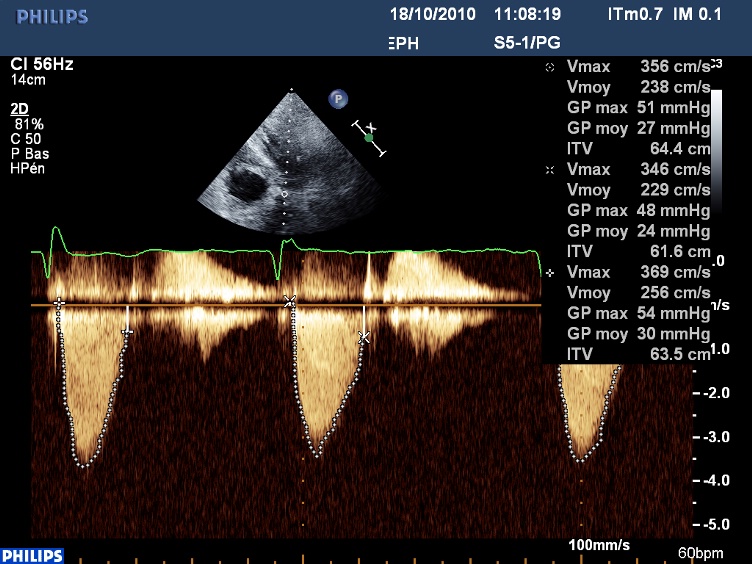

En Doppler continue, on peut obtenir le flux d’IM et celui d’obstacle intra ventriculaire gauche sur la même image :